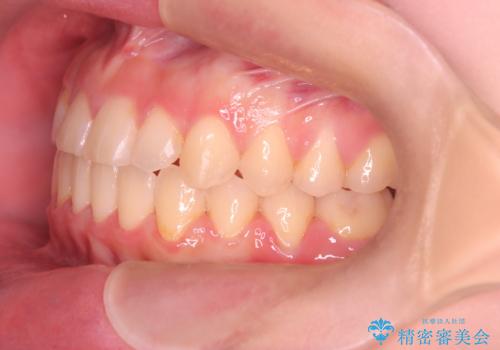

【ワイヤー矯正】一番後ろの奥歯でしか噛んでいないかみ合わせを治したい

最初は、一番後ろの奥歯でしか噛んでいない状態で、上下の前歯の先端がちょうど当たる切端咬合でした。

口腔習癖の改善及び、ワイヤー矯正にて歯列の平坦化を行うことで咬合を確立することができました。